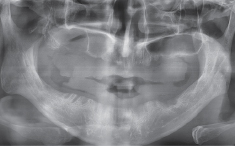

수술 전 파노라마

수술 후 파노라마